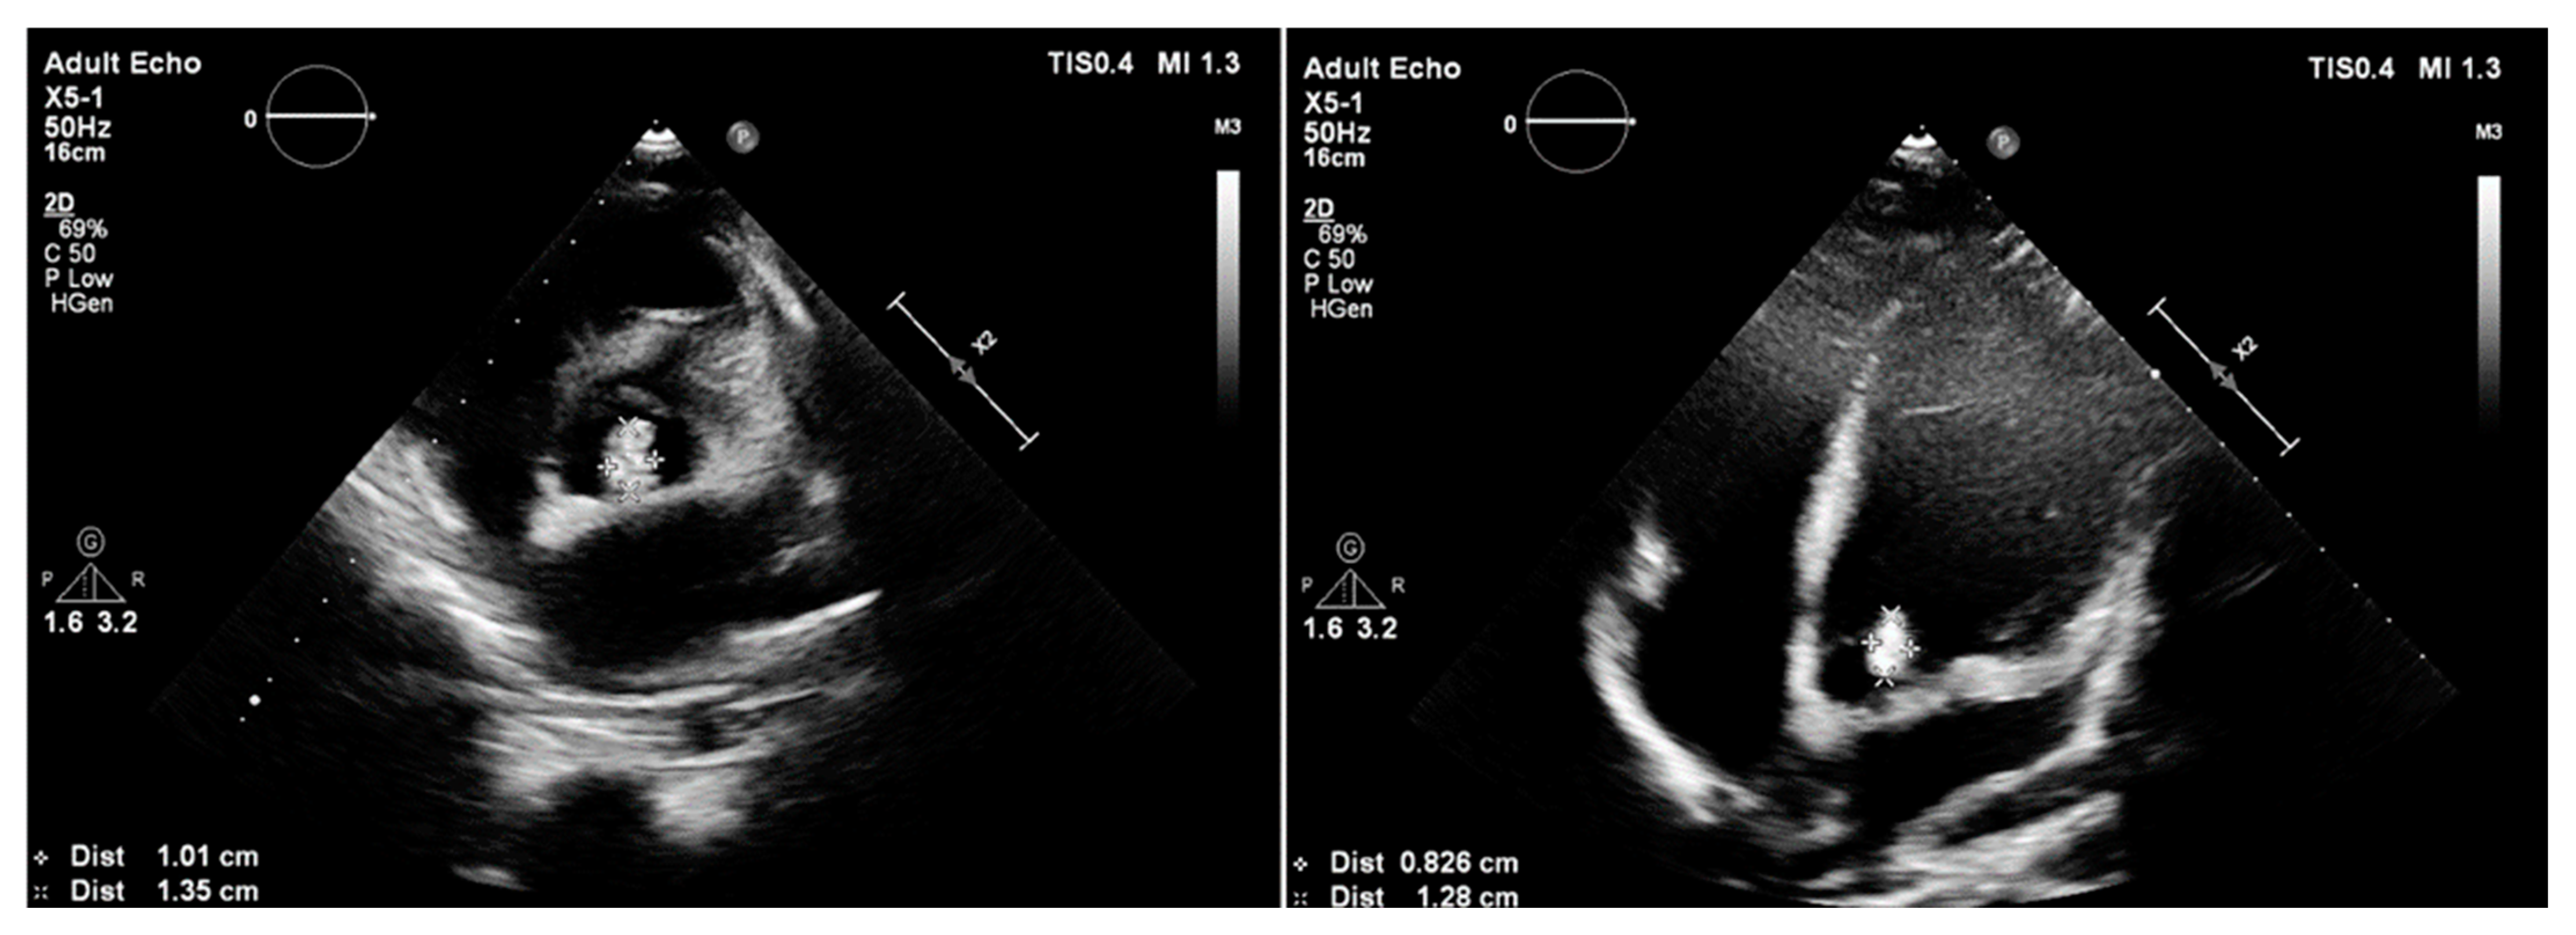

3.3. Case 3